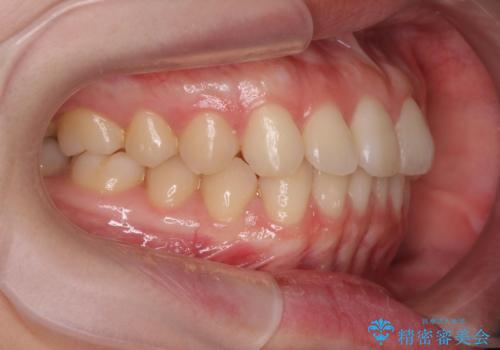

前歯のねじれをマウスピース矯正で治したい

- 前歯のねじれや がたつきを治したい、マウスピース矯正治療を希望され来院されました。

初診時程度のがたつきやねじれであれば、26枚以下のマウスピース矯正 モデレートプランで、比較的リーズナブルに矯正治療を受けていただくことができます。

実際の治療期間は約半年で仕上がりのような綺麗な歯並びを手に入れることができました。